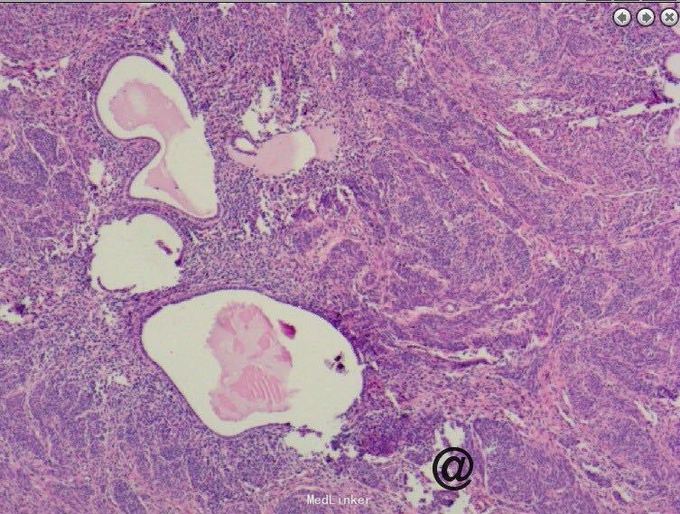

请妇科会诊,该科医师行妇检未见明显包块,且CA125正常,建议行小肠检查,同时行彩超探查了解包块来源,妇科彩超:子宫较小,宫体后壁肌壁间肌瘤(稍凸向宫腔),右侧附件区实质性包块,考虑为右侧卵巢肿瘤,左侧附件区未见明显异常显示,盆腔未见明显积液。 请妇科商议并于患者沟通后于2015.10.08转入妇科,转科行积极完善术前准备,于10.16行剖腹探查术。术中见:子宫稍大,质硬,后壁与直肠致密粘连,左侧卵巢大小正常,右侧卵巢增大直径约4cm,双侧附件与子宫后壁及盆壁致密粘连,分离盆腔粘连后可见巧克力样液体,阑尾可见约9*5*4cm肿瘤,包膜完整,与周围组织无粘连。请胃肠外科主任上台会诊,行阑尾切除术,术中快速病理切片检查示:(阑尾)腺上皮高级别上皮内瘤变(腺上皮中-重度异型增生),确诊待常规。再次向家属交代病情,将快切结果告知患者家属,患者家属了解病情,要求切除右半结肠,切除全子宫及双侧附件,最终行:全麻插管下行右半结肠根治性切除+肠粘连松解+腹式全子宫切除+双侧卵巢输卵管切除术。术后病检提示:(阑尾)中分化腺癌,癌浸润达肌层。阑尾手术切缘未见癌组织。免疫组化:CK19(+),Ki-67 LI约60%。子宫附件及右半结肠:1.送检肠管粘膜组织呈慢性炎,粘膜下水肿,纤维脂肪组织增生,血管扩张、充血。肠周触及淋巴结13枚呈反应性增生。 2.子宫腺肌症,囊性萎缩性子宫内膜组织,慢性子宫颈炎伴鳞状上皮化生。 3.(双侧)卵巢白体形成,(右侧)符合子宫内膜异位囊肿;(双侧)输卵管组织呈慢性炎,(右侧)伴系膜囊肿。

阑尾癌比较少见,以类癌多见,约占90%以上,腺癌罕见。类癌是胃肠道恶性肿瘤的一种,瘤体小,生长也慢,症状常不明显,亦可发生转移。类癌并不多见。如果类癌瘤体分泌释放肽胺类激素,患者就会出现腹痛、腹泻、哮喘、肝肿大等症状,医学上称为类癌综合征。阑尾炎很少发生此征。类癌各个年龄均可发病,平均发病年龄为40岁。阑尾类癌的恶性程度低,瘤体小,直径多在2厘米以下,且极少发生转移。阑尾类癌大多生长在距阑尾顶端1/3处,故不易堵塞阑尾管腔,很少引发阑尾炎。如果类癌生长在阑尾中1/3处,则多因堵塞管腔而发生阑尾炎。手术中,由于瘤体小,易不发现或误认为粪石,病理检查后方能得出正确诊断。阑尾类癌还可有阑尾穿孔表现,一般手术后才发现是阑尾类癌穿孔。本例发现腺癌,中分化程度,经切除后患者恢复良好,查国内文献偶尔有粘液性阑尾癌患者报道。本例手术前曾行肠镜检查观察阑尾内口无明显异常,分析考虑患者病变靠近阑尾顶端可能。所切除大体标本阑尾外膜尚完整光滑,咨询病例科医生诉患者阑尾肌肉组织层含有很多纤维增生成分。国外文献有报告甚少,多以类癌报道为主,近期看见一篇阑尾印戒细胞癌的case report!(Primary signet ring cell carcinoma of the appendix: A rare case report. World J Clin Cases 2015年 3卷 6期 538-41页 Primary adenocarcinoma of the appendix is a rare malignancythat constitutes < 0.5% of all gastrointestinalneoplasms. Moreover, primary signet ring cell carcinomaof the appendix is an exceedingly rare entity. In the present report, we describe a rare case of primary signet ring cell carcinoma of the appendix with ovarian metastasesand unresectable peritoneal dissemination occurring in a 45-year-old female patient. She was clinically misdiagnosed as torsion of ovarian cyst. She underwent appendicectomy and unilateral salpingo-oophorectomy.Histopathology revealed signet ring cell carcinoma and a right hemicolectomy was done. She then received palliative systemic chemotherapy with 12 cycles of oxaliplatin, 5-fluorouracil, and leucovorin (FOLFOX-4). The patient is doing well till today on follow up without progression of disease 10 mo after beginning chemotherapy. )